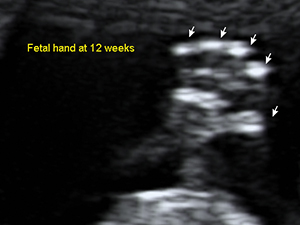

懷孕12週的胎兒手掌